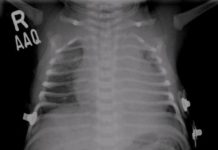

Chest radiography of a 2-month-old baby shows multiple bilateral rib fractures of different ages. Left-sided rib fractures (arrowheads) appear to have callus formation, while the right sided fractures (arrows) do not. Note right pleural effusion/thickening laterally.

Our case: non-accidental injury with multiple rib fractures in various stages of healing